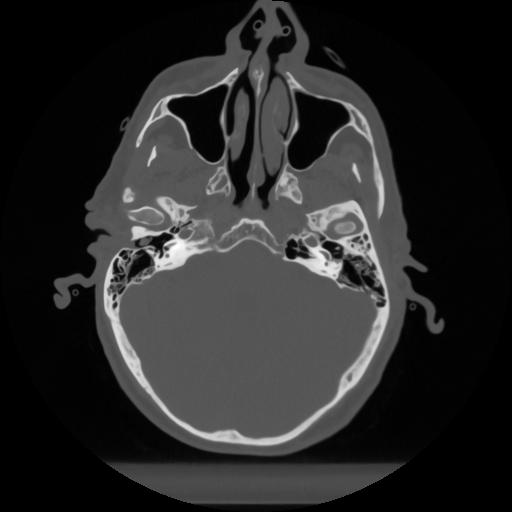

12 P.BLANDAS,,Vol,0.5,P.BLANDAS,,